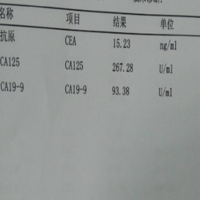

ca125偏高做试管能一次移植成功吗?

问题描述:我们结婚多年未育,准备做试管婴儿,前期检查已经完毕,结果检查CA125略高于正常值,我们在网上查了,说这个指标一点高都可以做试管,想问问移植的话能一次移植成功吗?最佳回答:ca125偏高可能会增加一些风险,但是如果卵子质量高、胚胎质量好,可能一次移植成功。医生会根据具体情况制定个性化的治疗方案。比如调整促排卵药物的剂量和使用时间,优化胚胎培养条件,以及加强子宫内膜的准备等,来提高成功率。...